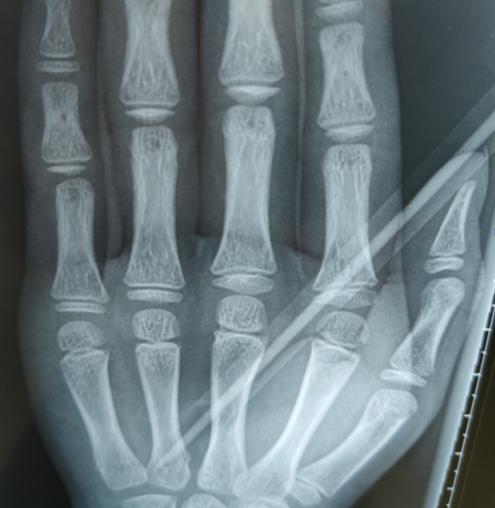

淼淼的妈妈和老师带着淼淼下午两点多才赶到我院,接诊的手外科三病区的李刚医生发现,铅笔斜着刺进淼淼的掌心2厘米,万幸的是没有导致“贯串伤”。

李刚医生手术团队立刻为淼淼进行了手术,术中探查见其血管、神经、肌腱已经部分损伤了。手术团队延长切口,小心取出铅笔,在显微镜下修复损伤的血管、神经和肌腱,并打上石膏。